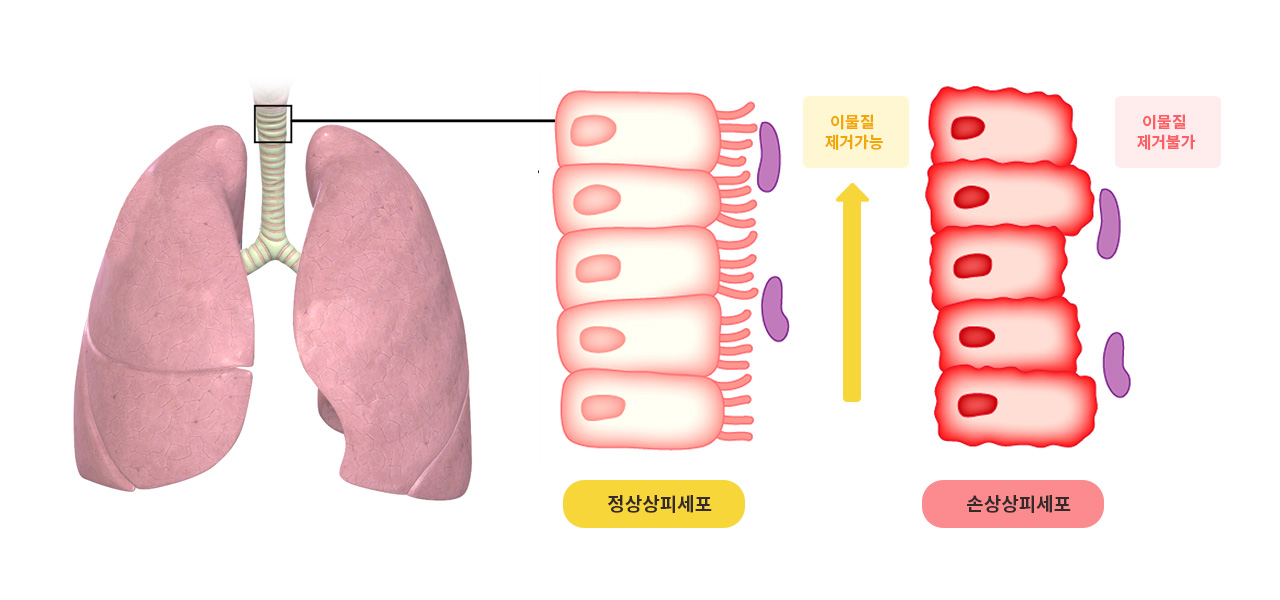

한약이 호흡기에서 일어나는 염증과정을 억제한다는 논문(중국)

Xia-bai-san inhibits lipopolysaccharide-induced activation of intercellular adhesion molecule-1 and nuclear factor-kappa B in human lung cells

Xia-bai-san (XBS) is a traditional Chinese medicine that has been used clinically for centuries in Asian countries to treat some types of common cold and asthma-like diseases similar to infantile pneumonia and childhood bronchitis. In previous studies, XBS was found to suppress the inflammatory process induced in lungs of mice treated with lipopolysaccharide (LPS).

Purpose: The present study was undertaken to examine the effects of XBS on LPS-inducible production of inflammatory cytokines, up-regulation of intercellular cell adhesion molecule-1 (ICAM-1), and activation of nuclear factor NF-kappaB in cultured human lung cells.

Principal results: Extracts of four raw herbs (Cortex mori, Cortex lycii, Radix glycyrrhizae, and Fructus oryzae) were used to prepare the decoction. XBS decreased the histological damage and up-regulation of ICAM-1 observed in lungs of mice treated with lipopolysaccharide (LPS). In cultured human pulmonary epithelial A549 cells, XBS and its components Morus alba and Glycyrrhiza uralensis suppressed the up-regulation of IL-8 and ICAM-1 in response to LPS. Production of TNF-alpha, IL-1beta, IL-6 and IL-8 by LPS-treated human THP-1 monomyelocytes was also suppressed by XBS. A549 cells expressed ICAM-1 in response to medium from LPS-treated THP-1 cells; expression was decreased by XBS. The adhesion of THP-1 cells to LPS-treated A549 cells were inhibited in the presence of XBS. Activation of NF-kappaB by LPS in A549 cells was suppressed by XBS, Morus alba, and Glycyrrhiza uralensis through inhibition of IkappaB phosphorylation; the concentrations at which suppression occurred were identical to those at which production of inflammatory cytokines and up-regulation of ICAM-1 were inhibited.

Major conclusions: These findings support the hypothesis that XBS, Morus alba, and Glycyrrhiza uralensis inhibit the inflammatory process in lung tissue through suppression of the IkappaB signaling pathway. XBS may prove helpful in the management of asthma, various allergic disorders, sepsis, or any other condition associated with pulmonary inflammation.